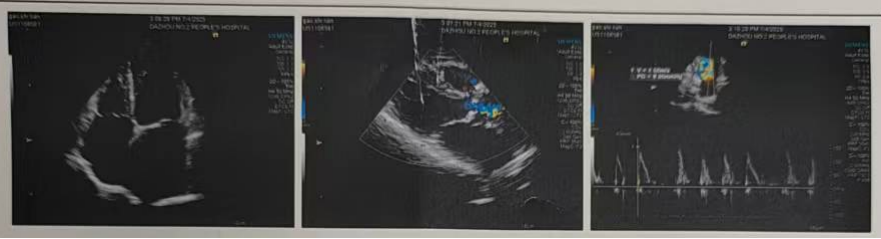

术前超声

术中,我院心血管内科、手术麻醉科、介入医学科、超声医学科、ICU、呼吸与危重症医学科、胸心血管外科、输血科等医护专家组成“护心团队”,在四川大学华西医院心血管内科魏家富教授团队的指导和护航下,经股动脉入路建立工作路径,成功置入新的人工主动脉瓣(VenusA-Plus瓣膜)。术后造影及超声提示未见明显反流,无瓣周漏,瓣膜置入位置良好,形态完整,术后跨瓣压差及舒张压即刻改善,未出现相关并发症,手术圆满成功。目前,患者已顺利出院!

术后超声